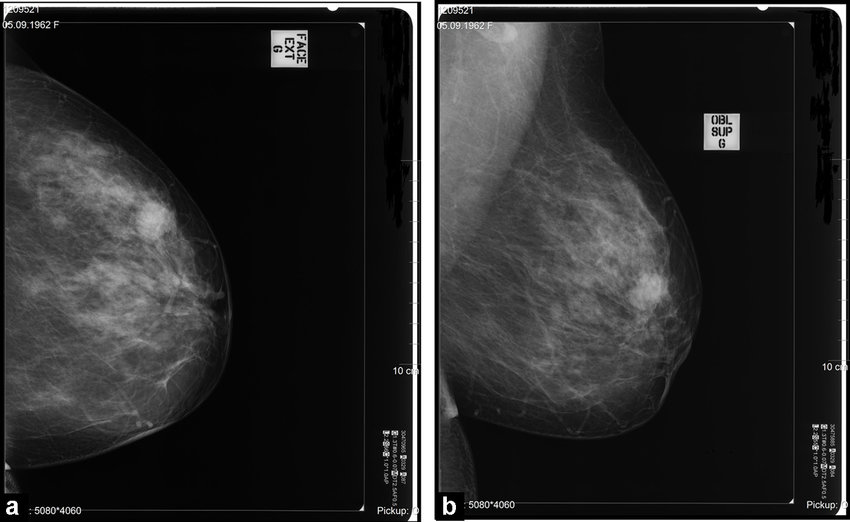

Una mamografía es una radiografía de la mama. En pocas palabras, su seno se encaja entre dos placas de plástico o vidrio, y se toma una exploración de rayos X para buscar crecimientos o tumores en el tejido. Son una herramienta útil porque a menudo pueden detectar el cáncer de mama en sus primeras etapas antes de que se desarrollen los síntomas.

Hay dos tipos principales de mamografías: de detección y de diagnóstico (Magny, 2020).

Mamografías de detección: este tipo busca signos de cáncer de mama. Esta mamografía anual de rutina se recomienda para mujeres de 40 años en adelante sin signos de cáncer de mama.

Mamografías de diagnóstico: se usan cuando hay un cambio en su mamografía de detección o si experimenta otros síntomas (bulto nuevo, dolor, engrosamiento o secreción del pezón, cambio en la piel). La mamografía de diagnóstico también se puede usar como una herramienta de detección para mujeres que han tenido cáncer de mama en el pasado.

Por lo general, las mamografías producen una imagen bidimensional en blanco y negro del seno. Sin embargo, las mamografías 3D (llamadas tomosíntesis de seno) son una opción más reciente. En lugar de presionar el seno dos veces, solo se presiona una vez. Se toman múltiples imágenes a medida que la máquina escanea el seno antes de compilarlas en una vista 3D.

Todavía se están explorando los beneficios potenciales de la mamografía 3D. Sin embargo, la investigación sugiere que pueden detectar más cánceres de mama y pueden reducir la necesidad de pruebas de seguimiento. Estos también pueden ser una mejor opción para las personas con senos densos (Rose, 2013; Svahn, 2015).